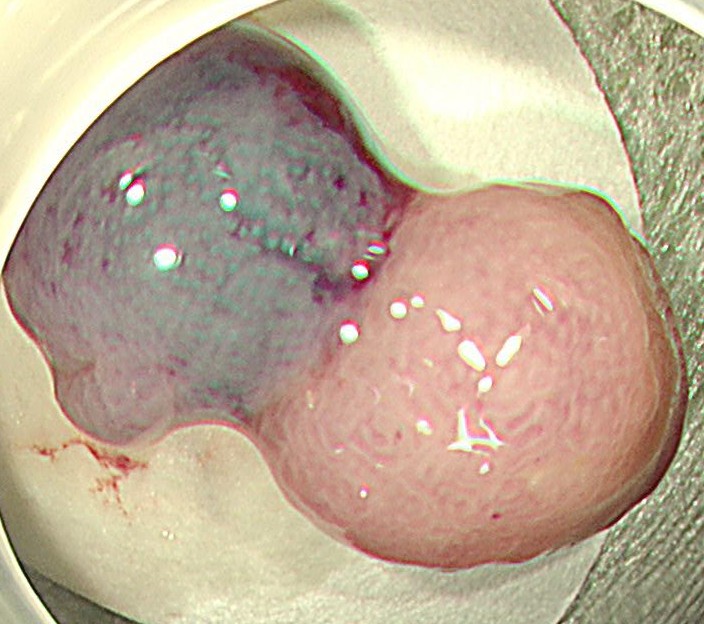

中年女性、下血にて来院。大腸内視鏡をしますと、直腸に15mm大のポリープを認めます。NBI(狭帯域光観察)では構造異形は乏しく、良性ポリープと診断しましたが、下血原因と考え、型のごとく内視鏡切除(EMR)しました。

病理診断にて直腸のSSA/P (sessile serrated adenoma/polyp 鋸歯状腺腫) と診断されました。大腸の鋸歯状腺腫はよくみられる病変ですが、右側結腸に多く、直腸は過形成性ポリープがほとんどで、直腸SSL (鋸歯状病変)は比較的まれです。またその多くが平坦な病変であるため、上記のようなⅠ型のポリープ形状は珍しい病変と思われます。最近の研究結果で直腸の隆起型のSSA/Pはがん化率が高いとする報告も散見され、注意を要する病変と思われます。